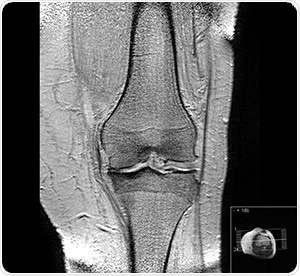

Bone cross-section by Pbroks13 [CC BY 3.0], via Wikimedia Commons

Recent studies on osteoarthritis have led to the belief that changes to the subchondral (below the cartilage) bone structures, like thickening of the subchondral plate, are apparent prior to lesions or other symptoms becoming obvious in the cartilage itself.

The current standards giving recommendations on the diagnosis and treatment of osteoarthritis depend on radiographic imaging to detect either of two things. First, the hardening of the subchondral layer, or second, a reduction in joint space and visual and tactile inspection during arthroscopic surgery.